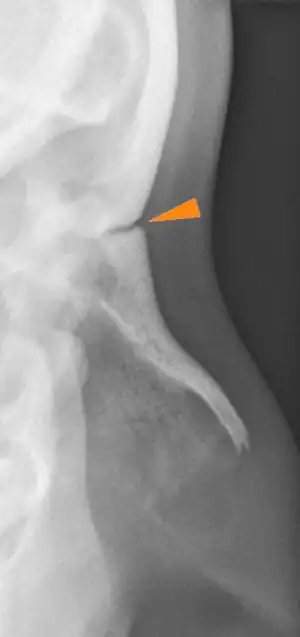

La suture fronto-nasale (ou suture naso-frontale) est la suture crânienne entre la partie nasale de l’os frontal et les bords supérieurs des deux os nasaux.